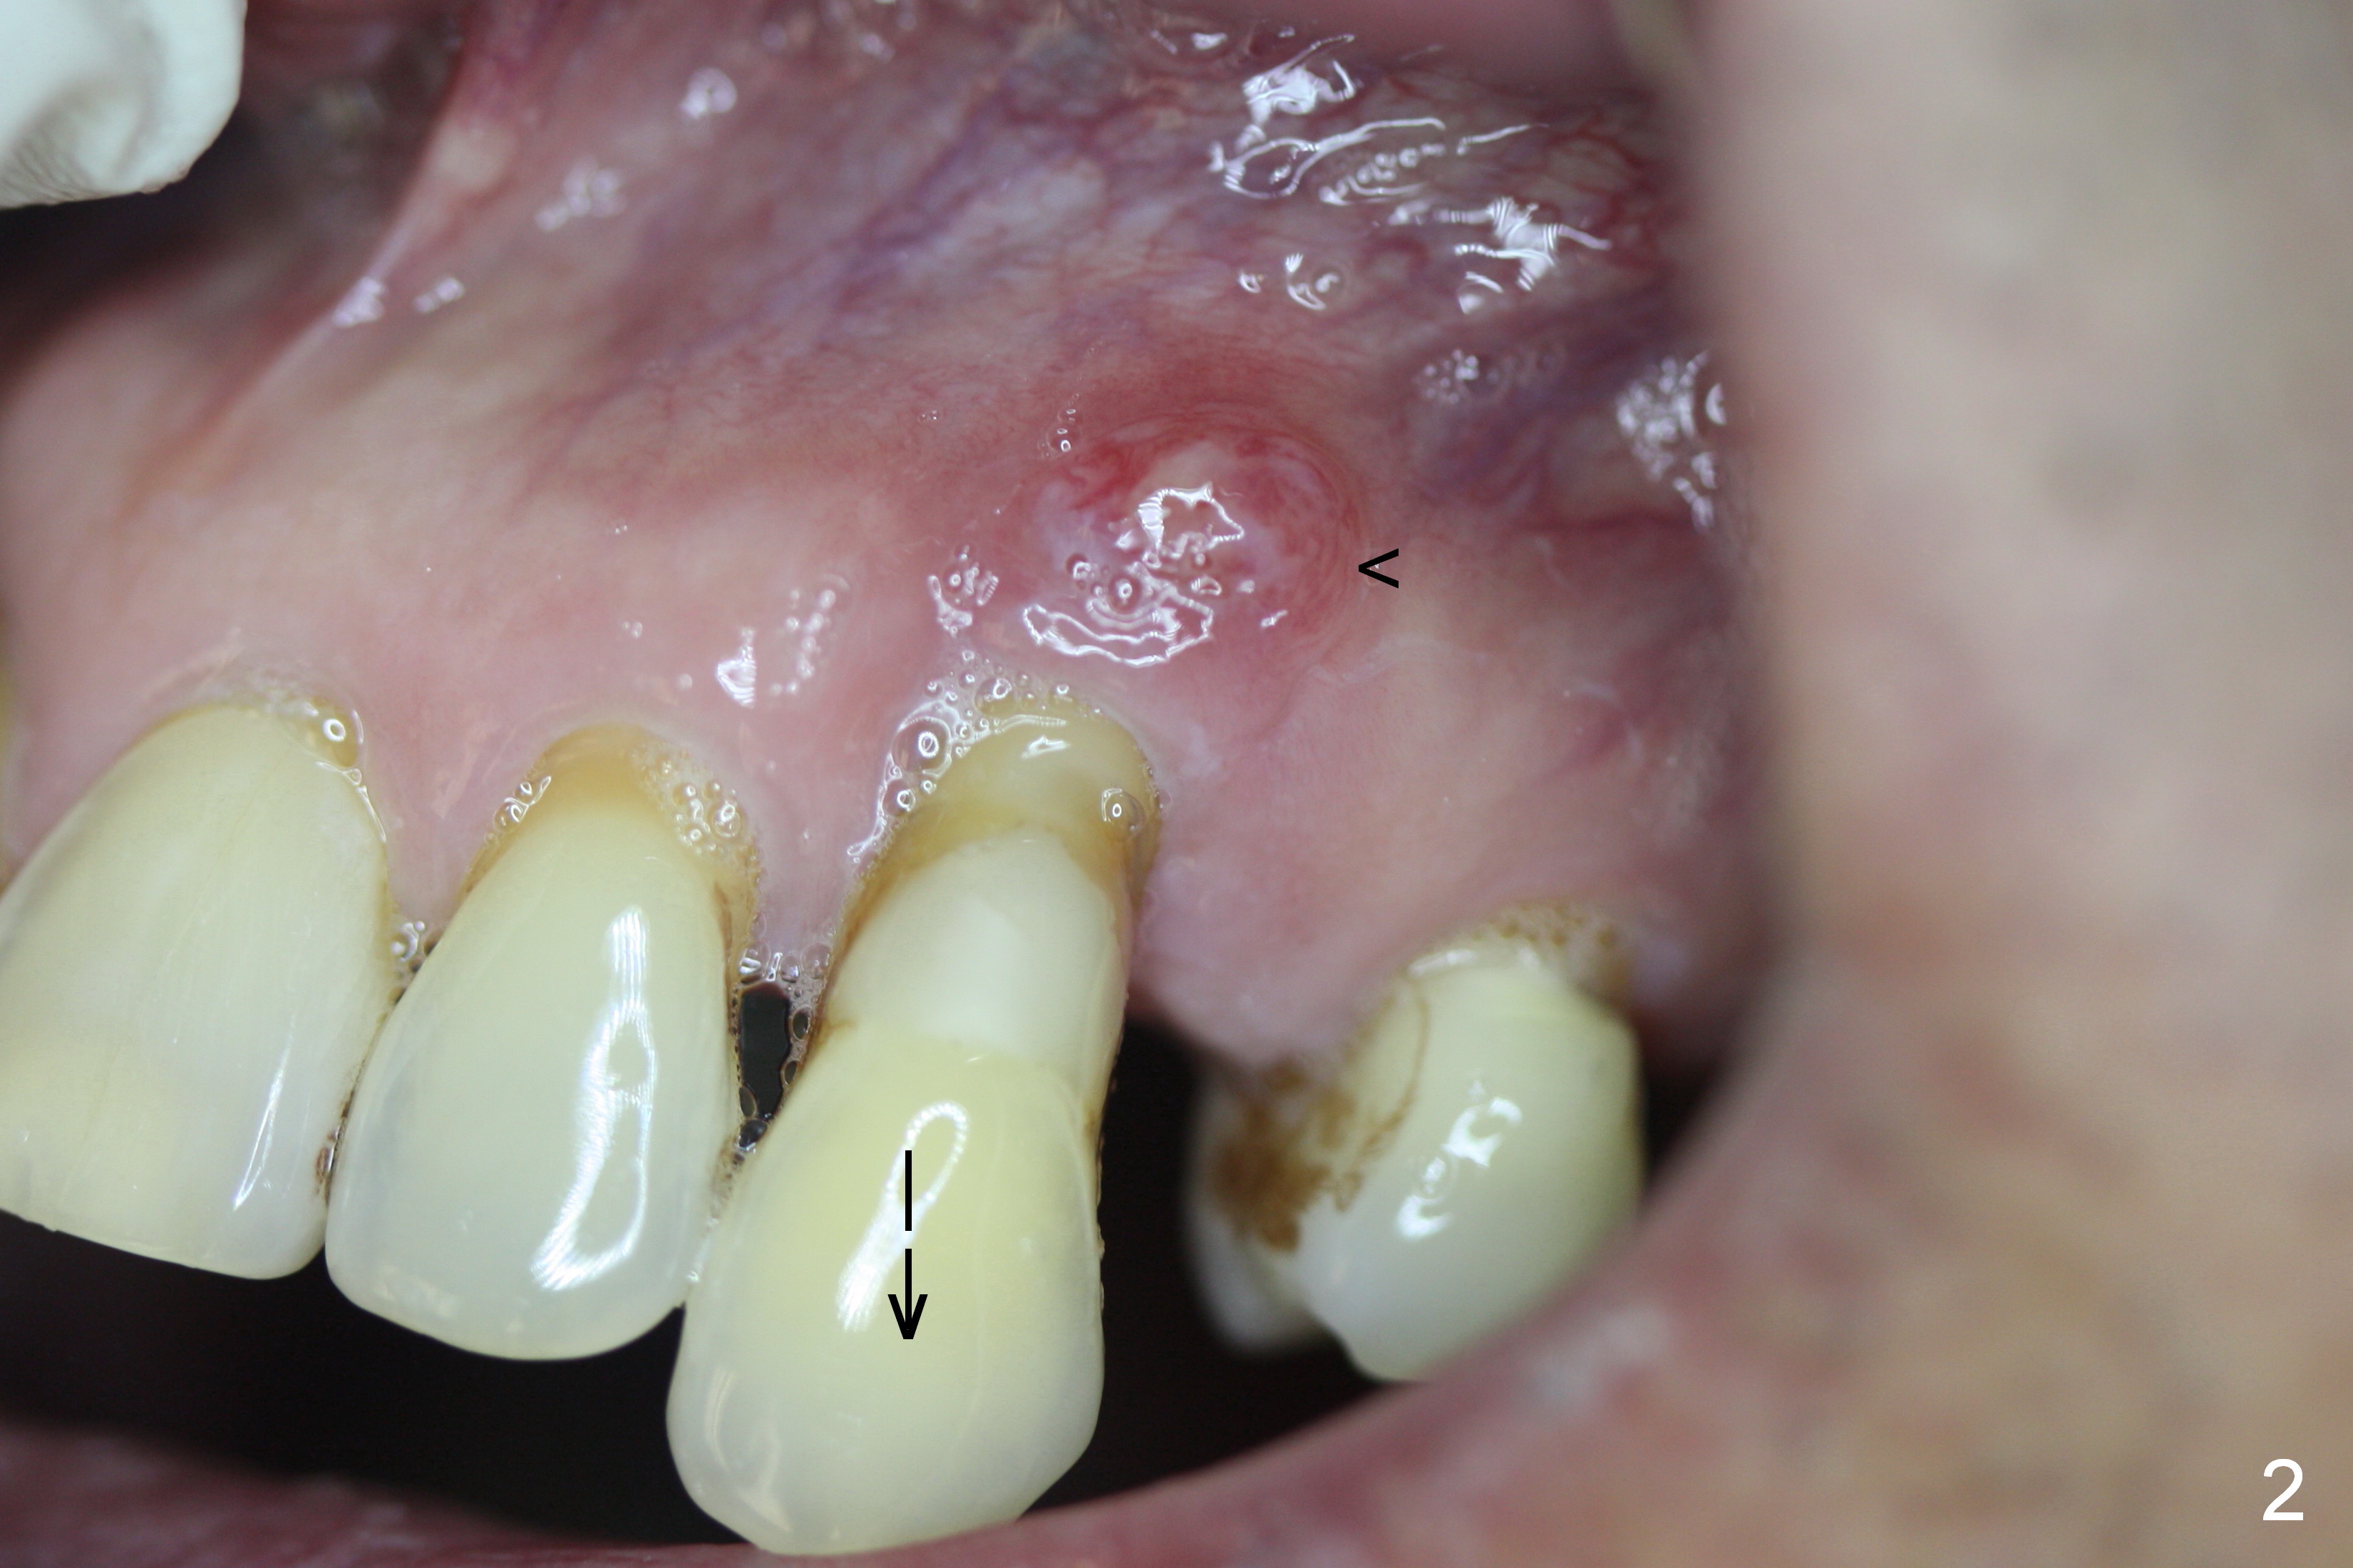

A 65-year-old man has history of Type II diabetes and stroke. He is taking a blood thinner (Xarelto 20 mg qd). The tooth #11 has been mobile for several years. Fig.1 is a CBCT taken 2 years 8 months earlier. The affected tooth has now supraerupted (Fig.2 arrow) with apical abscess (arrowhead).